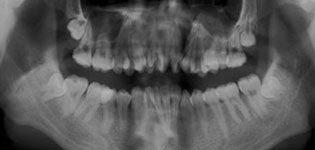

牙齿缺失后,若较长时间不修复,邻近的牙齿由于失去了依靠和约束,会变得倾斜,易造成咬颌功能的紊乱。

牙缺失后正常咬颌力对牙槽骨的生理性刺激不复存在,牙槽骨均会出现不同程度的废用性萎缩,并且会给后期假牙修复及维持口腔颌面部的平衡和稳定带来巨大困难。

牙齿缺失后,余留牙齿发生了一系列变化,使原本良好的咬颌关系发生变化,由于余留牙之间有效功能面积相应减少,咀嚼效能降低。

正常牙齿与牙齿之间,排列得十分紧密,邻近的牙齿移动后,牙齿与牙齿会出现缝隙,容易使食物嵌塞到牙齿间隙里,引起口臭、龋齿、牙周病等。

由于缺牙左右两边的牙齿无法获得它们原先常有的支撑压力,它们会在牙龈中变得倾斜不正,使牙齿逐渐松动,导致部分牙齿脱落。